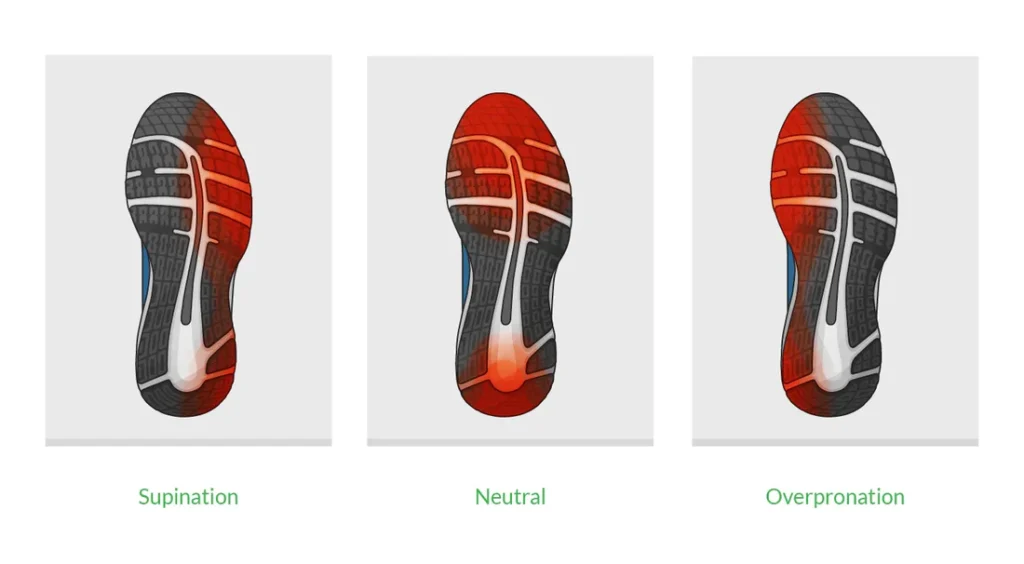

Overpronation and supination are biomechanical foot issues that affect walking and running posture. Overpronation occurs when the foot rolls inward excessively while walking, causing the arch to flatten. This can lead to ankle, knee, hip, or back pain due to misalignment. Supination, also called underpronation, is when the foot rolls outward too much, placing extra stress on the outer edge of the foot. It often leads to ankle sprains, shin splints, or heel pain. Both conditions can result from genetics, improper footwear, or muscle imbalances. Treatment involves wearing supportive shoes, using custom orthotic insoles, and performing strengthening and stretching exercises. Identifying and correcting these gait abnormalities early can help prevent further injury and improve overall foot and joint health.

Uneven wear may indicate alignment or gait issues.

Stand barefoot and look at your feet from the back. If the ankles roll inward or outward, that may indicate pronation/supination.